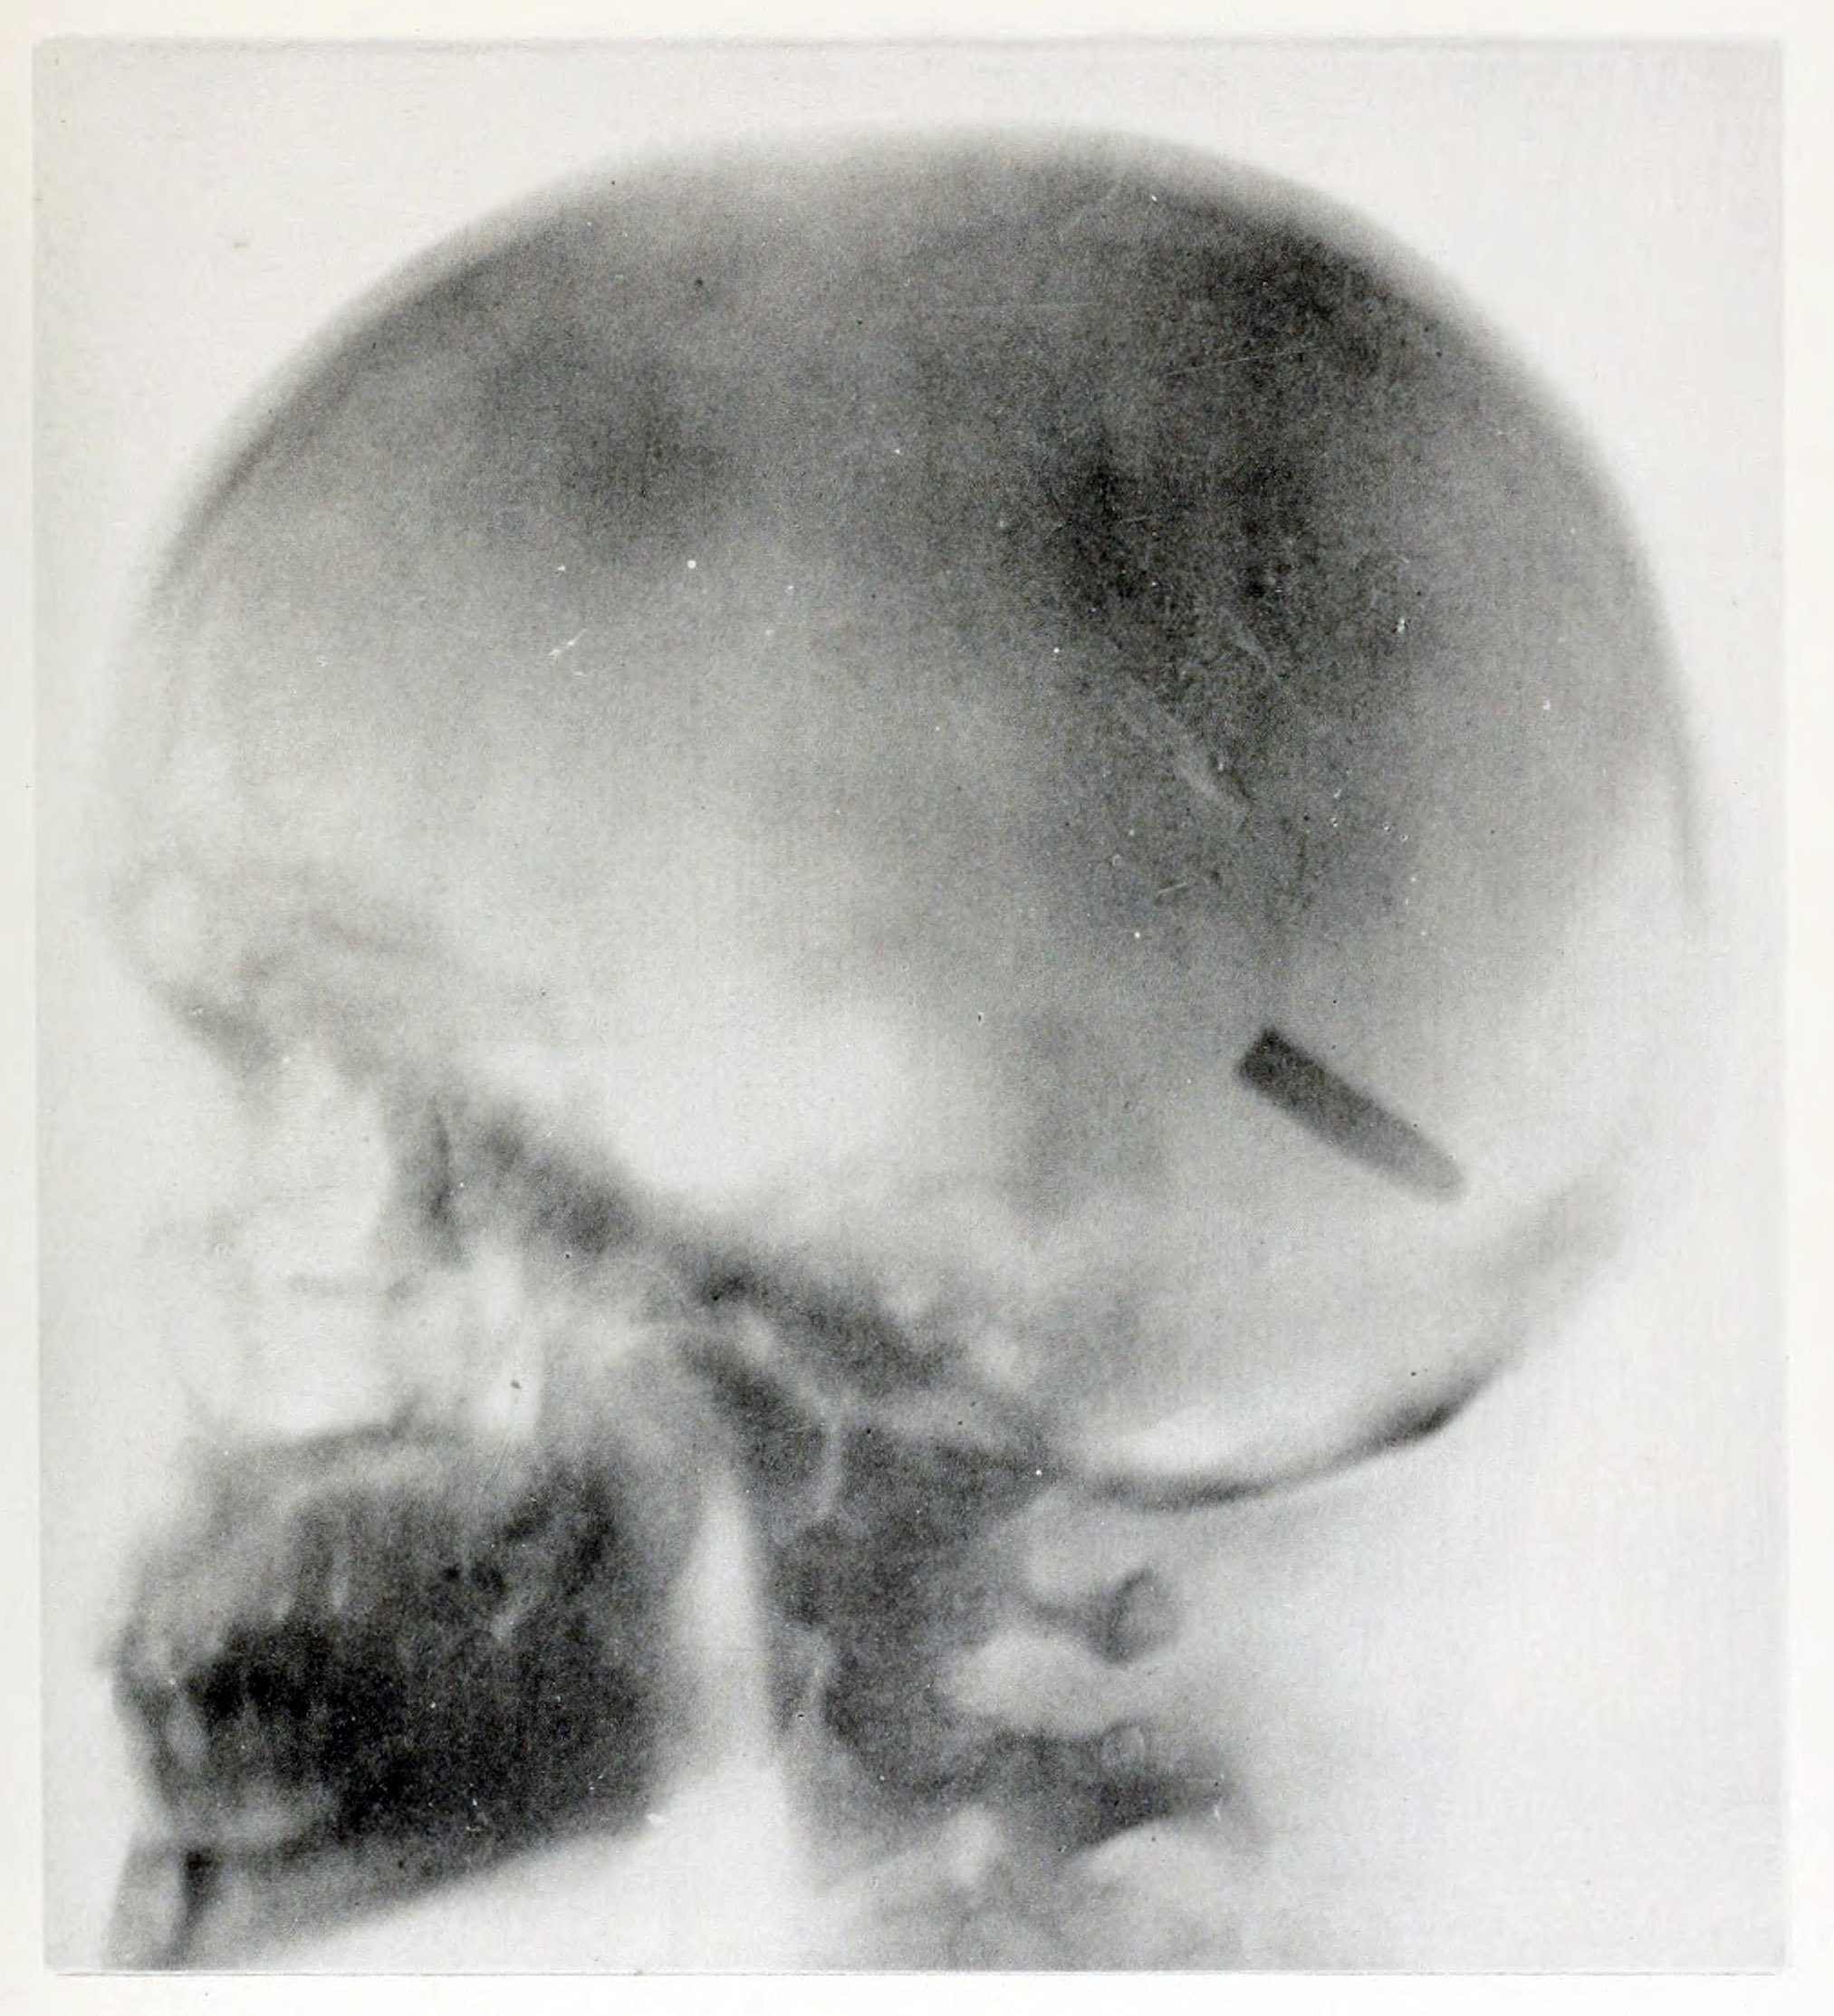

5. Elizabeth Fleischman, pionnière et autre victime tragique des rayons X

Elizabeth Fleischman était une pionnière de la technologie des rayons X. Son travail de radiographe pour l’armée américaine a produit certaines des images les plus célèbres de la radiologie médicale. Ironiquement, elle était également chargée de développer des mesures de protection contre les rayons X. Son dévouement l’a exposée à des niveaux de radiation mortels. En 1905, un an après la mort de Dally, elle est décédée d’un cancer, après que son bras ait dû être amputé l’année précédente à cause des dommages causés par les radiations. Sur sa pierre tombale, on peut lire : « Je pense que j’ai fait du bien dans ce monde ».